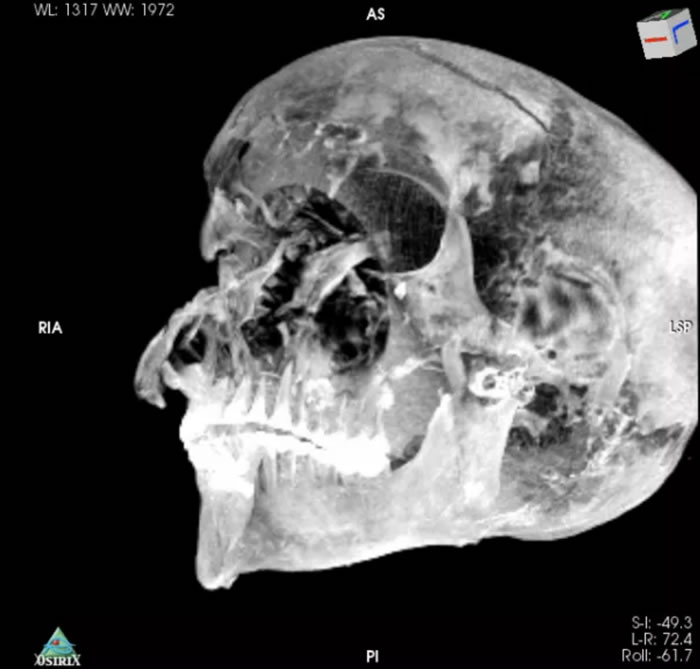

考古学家扎希·哈瓦斯与开罗大学医学院教授萨哈尔·萨利姆17日发表在期刊《医学前沿》上的研究成果显示,通过对木乃伊进行CT扫描并重建二维、三维图像,这两位学者发现,塞格嫩拉双手变形,头部伤痕被木乃伊制作者隐藏在一种防腐材料下,这些伤痕与埃及国家博物馆现存的希克索斯人使用的斧头、匕首等相吻合。

哈瓦斯表示,CT扫描技术可以更加安全、无创地研究木乃伊,更精准地判断死亡年龄及死因。

因为CT图像显示,法老王的头部左侧有另一组伤痕,但古代的防腐工匠巧妙地掩饰了Sequnenre的遗容,以至于1960年代的X光照都没能意识到这一点。